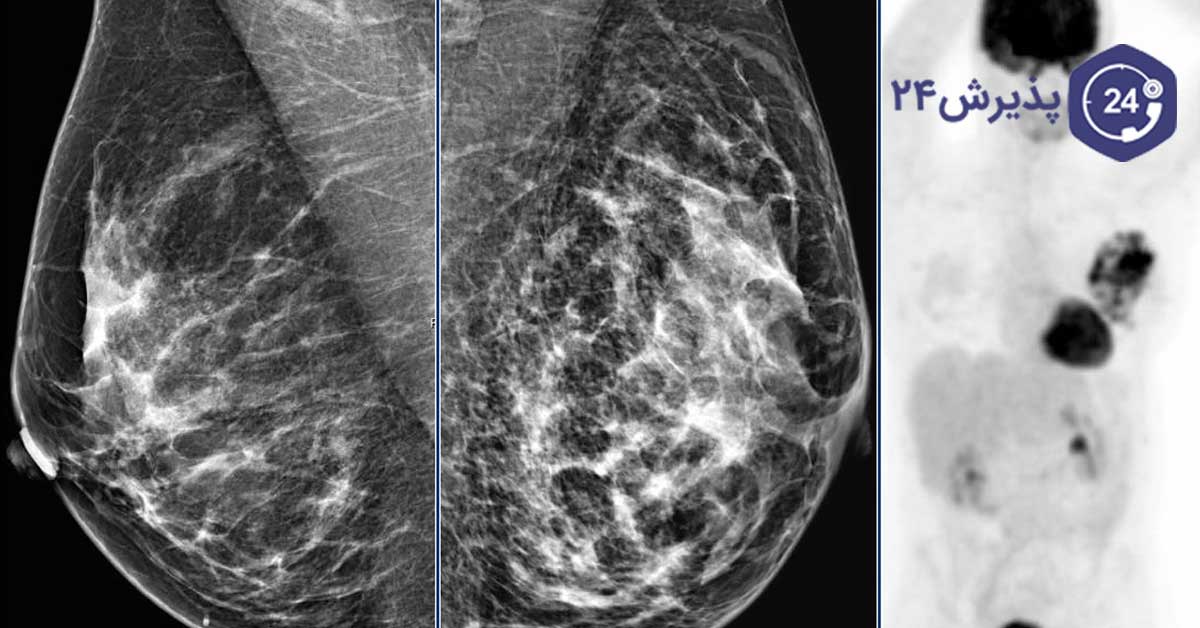

ماموگرافی یک روش عکسبرداری از سینه است که بهعنوان یک ابزار غربالگری تشخیص سرطان پستان مورد استفاده قرار میگیرد. همراه با معاینات منظم پزشکی و خود آزمایی ماهیانه سینه، ماموگرافی یک بخش کلیدی در تشخیص زودهنگام سرطان پستان بهحساب میآید.

حتی اگر فکر کردن به درد ناشی از ماموگرافی برای شما آزاردهنده است، با این وجود ماموگرافی سالیانه بعد از 40 سالگی برای زنان میتواند بهعنوان یک روش تشخیصی موثر حائز اهمیت باشد. در ادامه بهصورت مفصلتری شما را با روش تصویربرداری ماموگرافی آشنا میکنیم.

تصاویر حاصل از ماموگرافی که به صورت سیاه و سفید از بافت سینه شما گرفته شدهاند، قادرند رسوبات کلسیمی در سینه که با اصطلاح کلسیفیکاسیون (calcification) نامیده میشوند را شناسایی کنند. از روش تصویربرداری ماموگرافی بهمنظور مشاهده تودههای سرطانی و غیرسرطانی استفاده میشود. تودههای غیرسرطانی معمولا کیستهای طبیعی هستند که در طی چرخه قاعدگی ممکن است بهصورت گهگاه ایجاد شده و از بین بروند.